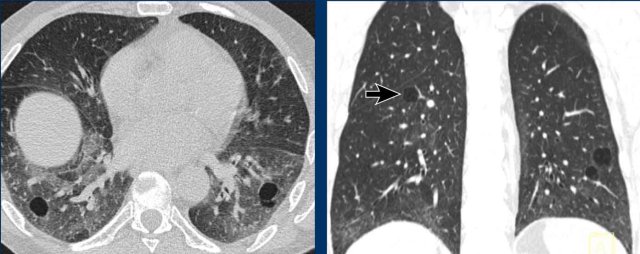

These images are of a 56-year-old woman, who had recurrent pneumothorax and now again presents with a pneumothorax (arrow).

Study the image.

Are these cysts or mimickers?

Is this an incidental finding or do you think it is a cystic lung disease?

What is the most likely diagnosis?

Findings

There are multiple thin-walled cysts - more than four. Notice the localisation near fissures and in the periphery of the lung.

Conclusion

This is a case of Birt-Hogg-Dubé syndrome (BHD).

Discussion

The two cystic lung diseases that frequently present with a pneumothorax, are LAM and BHD.

LAM presents as simple cysts, which are thin walled, round or oval and regularly shaped with a diffuse distribution.

The peripheral and perifissural location of BHD cysts often gives the cysts sharp angles that causes them to have a lenticular shape.

When cysts have this typical appearance, they have an extremely high specificity for the diagnosis of Birt-Hogg-Dubé syndrome.

This is another case of Birt-Hogg-Dubé syndrome.

The cysts are typically located in the periphery of the lung near the mediastinum (black arrow) and close to the fissure (white arrow).

This is another companion case with very few and small cysts in a patient with Birt-Hogg-Dubé syndrome.

Sometimes you need to study the lung fields very carefully not to overlook the cysts and miss the diagnosis of BHD.

In this case you can imagine, that if the CT is performed for another reason, that you can easily miss these tiny cysts.

Remember that when you see more than four cysts and they are truly  cysts, you need to do something with the findings.

These patients should go to a pulmonologist for further work up.